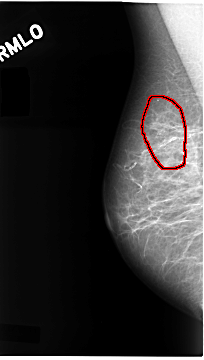

C_0099_1.RIGHT_MLO

RIGHT_MLO LINES 4680 PIXELS_PER_LINE 2648 BITS_PER_PIXEL 12 RESOLUTION 50 OVERLAY

FILE: C_0099_1.RIGHT_MLO.OVERLAY

TOTAL_ABNORMALITIES 1

ABNORMALITY 1

LESION_TYPE CALCIFICATION TYPE PLEOMORPHIC DISTRIBUTION CLUSTERED

ASSESSMENT 5

SUBTLETY 5

PATHOLOGY MALIGNANT

TOTAL_OUTLINES 1

BOUNDARY